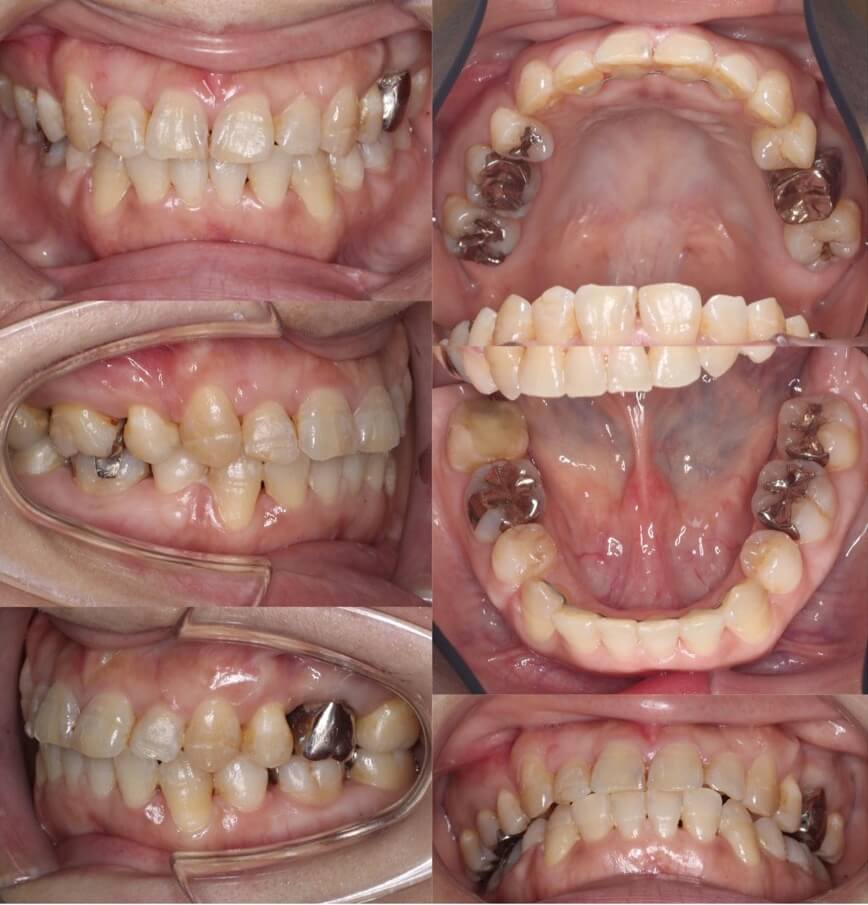

43歳女性・唇側矯正装置・抜歯

<症例概要>

主訴:前歯のがたつきと・かみ合わせ

年齢・性別:43歳女性

住まい:千葉県佐倉い市

症状:叢生・前歯交叉咬合・左上5番萌出不全

治療方針:右上下4番・左上下5番(計4本)

治療装置:唇側矯正装置

固定装置:リンガルアーチ

治療期間:2年6か月

リテーナー:下フィックス+上下クリアタイプ

治療費用:968,000(税込)

代表的副作用:痛み・治療後の後戻り・歯根吸収・歯髄壊死・歯肉退縮

▶︎その他の副作用

抜歯矯正ではふつう4番を抜歯するのですが、歯の状況によっては5番を抜歯することもあります。左上の5番の歯が半分弱しか出てきてないことと、左下の5番が大きく外側に転位していることから、左側のみ5番を抜歯し矯正治療を行いました。やや歯列の正中線は、4番を抜歯した右側に引っ張られたのですが、患者さんはそこまで気にしていませんでした。